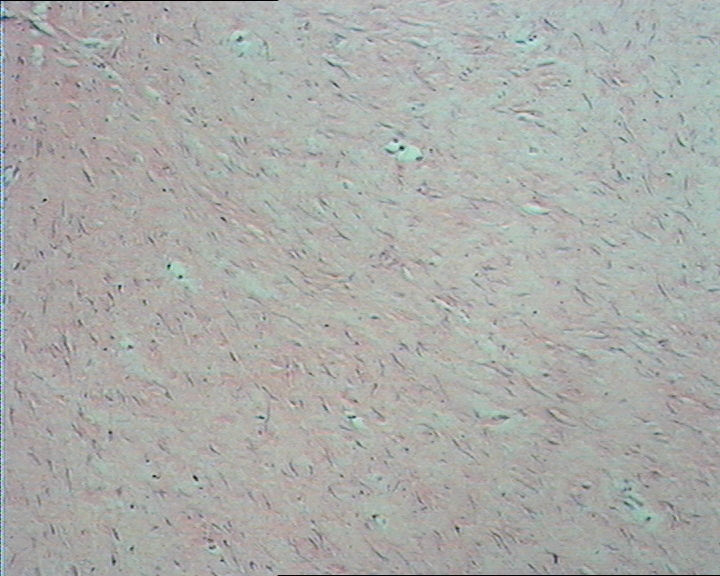

图3

无包膜 3.8cm*3.0cm*2cm 切面灰白淡黄相间

右肘部肿物,无包膜,3.8cm*3.0cm*2cm,切面灰白淡黄相间。